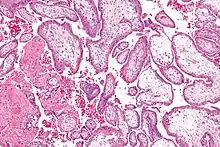

Vilosidades coriónicas (português europeu) ou vilosidades coriônicas (português brasileiro) são vilosidades que florescem na placenta a partir dos córios de forma a permitir o máximo de área de contacto com o sangue materno durante uma gravidez.[1]

Micrografia das vilosidades coriónicas